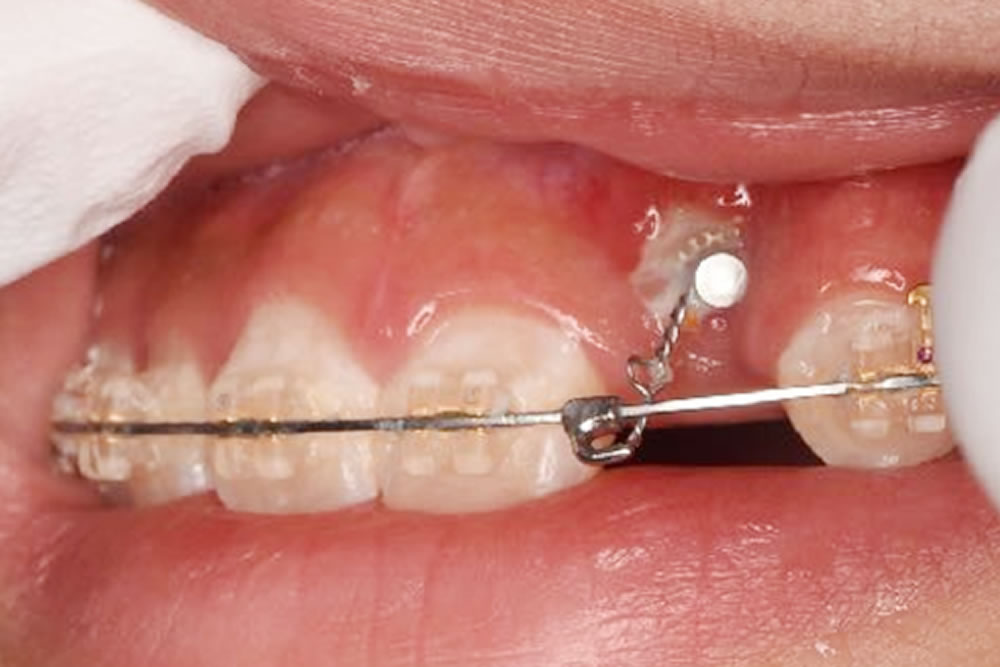

本症例では、残念ながら自然と萌出してくることがなかったため、矯正装置を変更し、マルチブラケット装置によるワイヤー矯正によって開窓牽引を行いました。

①CT画像にて外科的侵襲が最小限になるよう、開窓する部位を計画します。表面麻酔、浸潤麻酔をした後、電気メスにて歯肉を切除していきます。